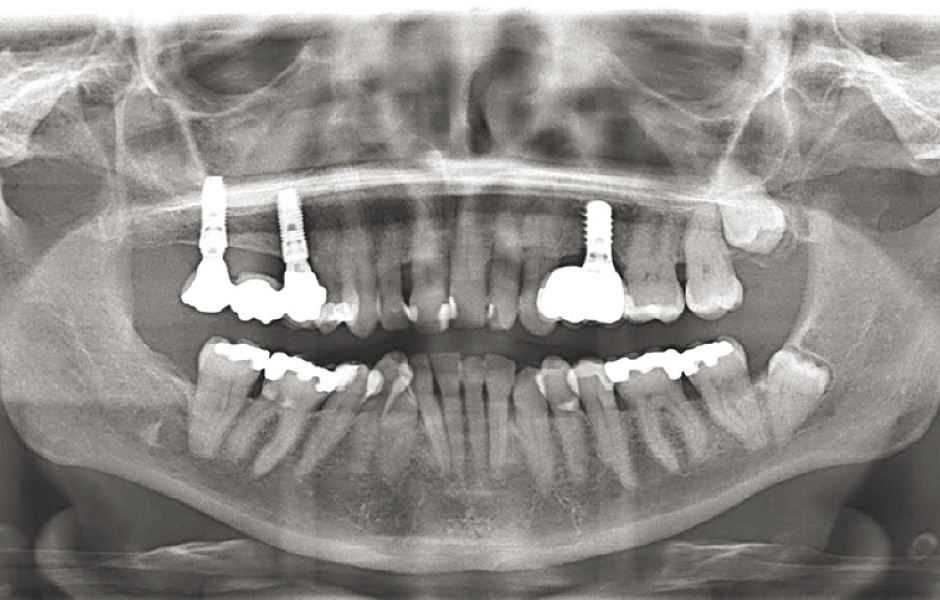

U všech 10 pacientů proběhla chirurgická léčba aspergilózy bez komplikací, což umožnilo provedení následných augmentačních výkonů. Všechny kostní a sinusové štěpy se zhojily bez obtíží. Do augmentované oblasti bylo tři měsíce po operaci úspěšně zavedeno celkem 26 implantátů, které byly proteticky ošetřeny podle stanoveného protokolu. Pacienti dodržovali přísný šestiměsíční recall systém a byli průběžně sledováni až 10 let, v průměru po dobu 78 měsíců. Implantáty vykazovaly dobrý stav, hloubka sondáže nepřesáhla 4 mm. Pooperační radiologické snímky neprokázaly žádné známky další sinusové infekce.

Obr. 6: CBCT po 10 letech od augmentace a zavedení implantátů ukazuje oblast bez recidivy.

Obr. 15: Panoramatický snímek po 5 letech: implantáty proteticky ošetřeny, oblast stabilní.